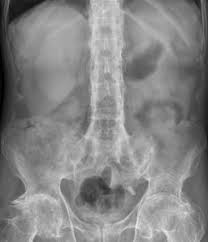

Rx lombar. Dor lombar intensa ou que dura mais de quatro a oito semanas. Rx coluna dorso lombar rx coluna lombo-sacra rx coluna para escoliose rx coluna sacro-coccix rx coluna total para escoliose telespondilografia rx condutos auditivos internos rx coracao e vasos da base rx costelas por hemitÓrax rx cotovelo rx coxa. Osteoartrite que é a artrite que afeta as articulações.

Em casos de RX com contraste poderemos necessitar de punção venosa ou sondagem a depender da indicação e avaliação prévia pela equipe responsável. Não tem preparo Unidade 1 Peso limite para a realização de RX é de 110 quilos. 30x40cm ou 35x43cm na longitudinal.